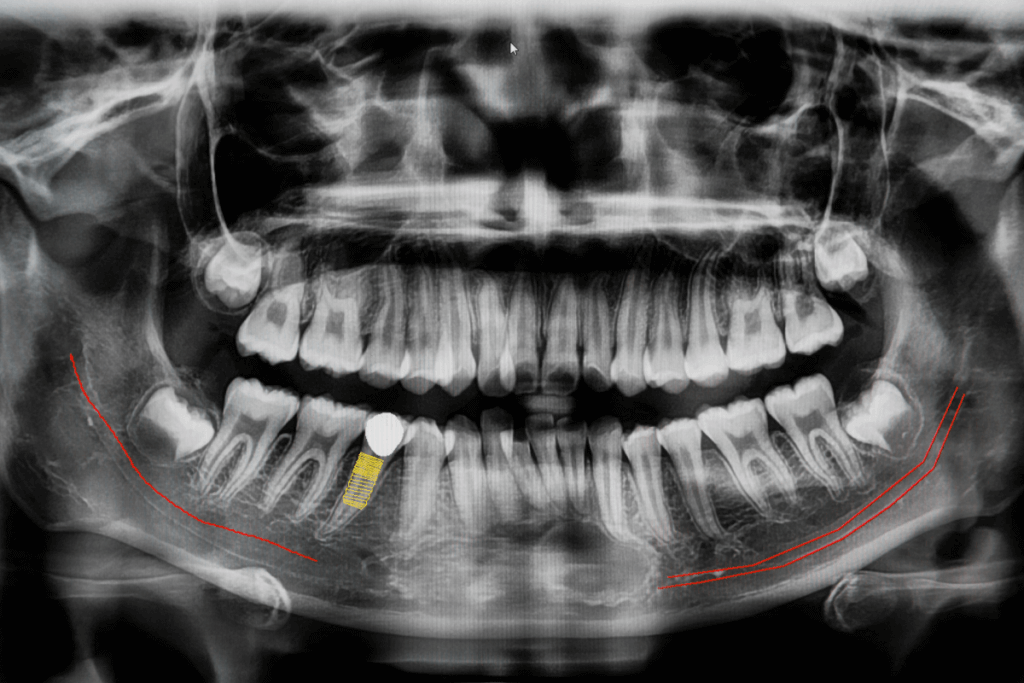

Ao utilizar imagens detalhadas obtidas a partir de tomografias computadorizadas (TC) ou escaneamentos intraorais, os cirurgiões podem explorar a anatomia bucal do paciente em profundidade. Isso inclui a análise minuciosa da estrutura óssea, a localização precisa dos nervos e outras estruturas importantes.

Essa tecnologia de imagem avançada fornece uma visualização completa e precisa da anatomia bucal, permitindo que os cirurgiões tenham uma compreensão profunda das estruturas ósseas, dentes adjacentes, nervos e outros elementos anatômicos cruciais.

As imagens 3D resultantes são detalhadas e precisas, permitindo aos profissionais explorar a região de interesse em diferentes ângulos e cortes. Isso possibilita uma análise minuciosa da densidade óssea, forma do osso, direção dos nervos e a relação com os dentes vizinhos. Essas informações são cruciais para tomar decisões informadas durante o planejamento do procedimento.

Com base na análise das imagens 3D, o cirurgião define as posições ideais para os implantes. Essa etapa é crucial para garantir uma distribuição adequada dos implantes, evitando riscos para estruturas sensíveis, como nervos e seios maxilares.